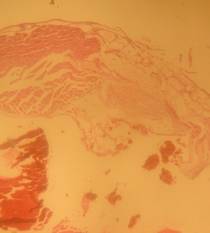

Histopathology

All rats were sacrificed, and their aortas were isolated for histological preparation. The aorta samples were fixed in 10% formaldehyde solution, and their slides were prepared. The slide preparations (6-8 µm thickness) were stained with hematoxylin/eosin. Each slide was scored based on the aorta conditions. The scores ranged from 0–4 with the following criteria: 0 normal condition; 1 if elastic fibres thickening was found; 2 if elastic fibres fragmentation, some foam cells, and fibrosis were found; 3 if smooth muscle proliferation was found, and 4 if plaque ulceration or plaque lipid calcification was found [10].

Morphological structure of aorta’s rats

Aorta’ slide was made every week for one month. Each group of the rats was killed, and the aorta’s rat was observed. From the morphological structure of aorta’s rat, atherosclerosis was scored as follows: on 4 point: 0, normal; 1, widening of elastic fibers with few foam cells; 2, fragmentation of elastic lamellae with numerous foam cells and fibrosis; 3, smooth muscle cells proliferation, medial lipid infiltration and fibrosis; 4, lipid-calcic plaque or ulcerated plaque [10].

The rats (n=4) from each group were sacrificed every week to observe the morphological structure of the aortas. From the lesions, it showed that AND could help chance severity aortic atherosclerosis. The score varied from group A1 until group A4. The aorta morphology of group A1 showed that one aorta had a widening of elastic fibers with few foam cells (score 1) and three aortas had the proliferation of smooth muscle cells (score 3) (fig. 5 A1). AND administration for four weeks could repair aorta condition. Group A4’ aorta morphology showed that three aortas became normal (score 0) and one aorta still had a widening of the first interlamellar (score 1) (fig. 5 A4). Atorvastatin administration could also help changing the severity of aortic atherosclerosis. The score also varied from group B1 until group B4. The aorta morphology of group B1 showed that one aorta had a widening of elastic fibers with few foam cells (score 1), two aortas had fragmentation of elastic lamellae with numerous foam cells and fibrosis (score 2), and one aorta had the proliferation of smooth muscle cells (score 3) (fig. 5 B1). Atorvastatin administration for four weeks could improve aorta condition. Group B4’ aorta morphology showed that two aortas became normal (score 0) and two aortas still had a widening of the first interlamellar (score 1) (fig. 5 B4). Contrarily, the morphological structure of atherogenic rats was getting worse week by week.

Fig. 5: Morphological structure of aorta in albino Wistar male rats 40x. A1, A2, A3, A4 is morphological structure of aorta’s AND rats fed atherogenic diet for 2 mo and continuing with AND for 1 w, 2 w, 3 w and 4 w; B1, B2, B3, B4 is morphological structure of aorta’s atorvastatin rats fed atherogenic diet for 2 mo and continuing with atorvastatin for 1 w, 2 w, 3 w and 4 w; C1, C2, C3, C4 is morphological structure of aorta’s rats fed atherogenic diet for 9th week, 10th week, 11th week, 12th week; D1, D2, D3, D4 is morphological structure of aorta’s rats fed regular diet for 9th week, 10th week, 11th week, 12th week. Black circle (O) = score 1; green circle (O) = score 2; red circle (O) = score 3; blue circle (O) = score 4